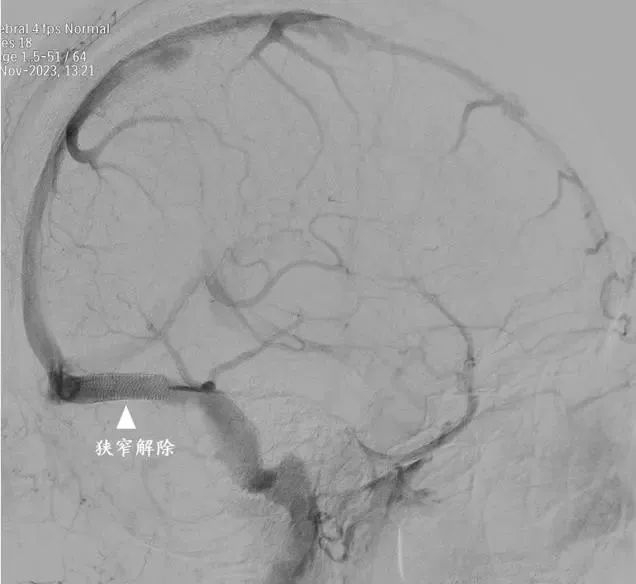

术后

手术非常成功,狭窄的静脉窦“天堑变通途”。吴女士全麻苏醒后,久违的笑容又回来了,头痛和头胀症状明显缓解了,视物也变得清晰了,左手麻木无力感完全消失。